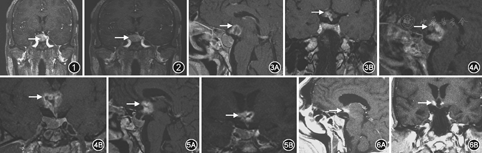

患者男,31岁,口腔科医师,因"肢端粗大10年,近2年加重"于2014年12月17日入住我院。患者面容进行性改变、手足进行性变大10年余,直至2013年5月才注意到肢端肥大面容改变,查随机生长激素(GH)>50 μg/L,磁共振成像(MRI)提示垂体瘤(2.5 cm×1.5 cm,图1)。2013年6月于外院行经鼻蝶垂体瘤手术,病理提示垂体GH瘤。2013年9月(术后3个月)复查MRI提示垂体GH瘤术后残余(图2),随机GH 8 μg/L,外院即行伽玛刀治疗(中心剂量:40 Gy,周边剂量:20 Gy,等剂量:50%,靶点数:20,治疗范围:95 mm×115 mm×100 mm)。其后肢端肥大体征较前无明显变化,未再复查GH和胰岛素样生长因子1(IGF-1)。2014年6月(术后1年、伽玛刀后9个月)出现乏力、嗜睡、精神恍惚、记忆力减退,症状逐渐加重,伴左眼视野缺损。查随机GH>50 μg/L,MRI提示垂体GH瘤术后残余(图3),视交叉、下丘脑出现异常强化影,呈边缘不规则花环状强化,病灶中央为无强化坏死区。2014年8月复查MRI提示下丘脑区病灶增大(图4),考虑放射性脑病可能,予以甘露醇250 ml加地塞米松2.5 mg治疗,精神好转,食欲增加。2014年12月停用,患者再次出现乏力、嗜睡、精神恍惚、食欲减退;复查MRI视交叉、下丘脑仍可见异常强化影(图5)。为进一步诊治入住我院。体格检查:推车入院,中度脱水貌,嗜睡,对答不切题;认知功能减退;典型肢端肥大体征:眉弓稍粗,鼻梁稍宽,上唇增厚,四肢肢端增厚增粗。

治疗经过和随访:予口服、静脉补液扩容治疗12 d,缓慢降低血钠,血肌酐,尿酸和三酰甘油恢复正常;予甘精胰岛素10 U睡前皮下注射,口服伏格列波糖0.2 mg/次,3次/d,瑞格列奈1 mg/次,3次/d控制血糖,监测血糖调整治疗方案;神经放射外科会诊,予醋酸泼尼松口服10 mg/次,2次/d;针对垂体GH瘤术后残留生化未缓解问题:神经外科、神经放射外科、内分泌科讨论后予以生长抑素类似物(SSA)注射用醋酸奥曲肽微球20 mg肌肉注射,每4周1次。住院期间患者精神体力好转,记忆力较前有所恢复,电解质恢复正常,血糖稳定,出院。2015年3月复查,患者记忆力、认知较前有所好转,但仍需人照顾,无法恢复正常生活。后期随访无视力视野缺损表现,体重增加10 kg;复查MRI下丘脑病灶较前明显缩小(图6);血糖控制良好,糖化血红蛋白5.6%;评价甲状腺轴(TSH、T3、T4、FT3、FT4)、性腺轴(睾酮、FSH、LH)和垂体后叶功能正常;口服葡萄糖耐量试验(OGTT)提示GH控制正常,IGF-1仍高于正常但较前下降(1 021 μg/L)。继续SSA、口服降糖药治疗和辅助治疗,逐步减少醋酸泼尼松剂量。